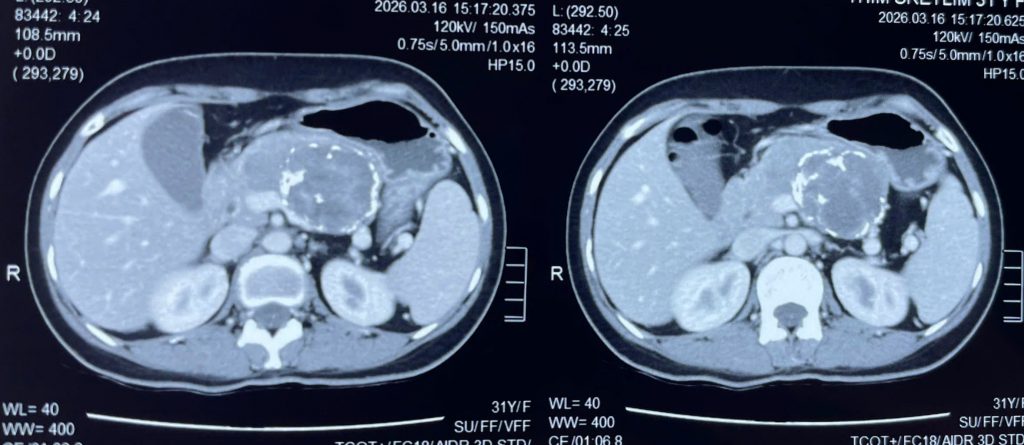

Bệnh nhân đến Bệnh viện Đa khoa Xuyên Á thăm khám trong tình trạng đau âm ỉ vùng thượng vị. Kết quả chụp CT và MRI cho thấy khối u tụy kích thước hơn 8.6 cm, chiếm gần toàn bộ tụy, chèn ép các mạch máu quan trọng nuôi gan.

Hình ảnh phim CT khối u tụy

Nếu không điều trị kịp thời, khối u không chỉ đe dọa chức năng gan mà còn tiềm ẩn nguy cơ tiến triển thành ác tính.